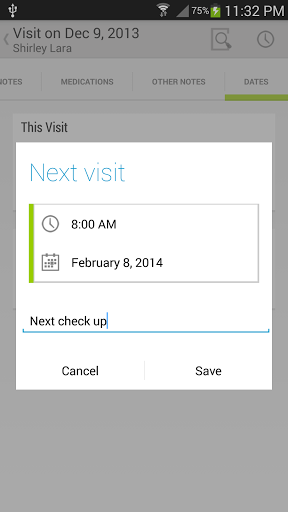

• Voir la visite du patient / antécédents médicaux

• Pendant les visites des patients, ajouter des notes de visite / médicales comme du texte, une image, un enregistrement vocal ou une écriture manuscrite